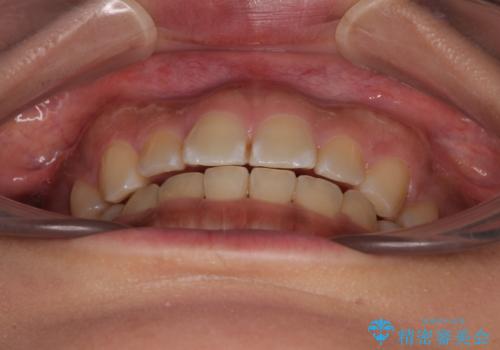

デコボコと捻れて前に飛び出した歯列 抜歯矯正でスッキリした口元に

- 前歯のデコボコと口元の突出感を気にして来院された患者様です。

非抜歯矯正ではデコボコを解消することでより口元が突出してしまうため、上下左右の小臼歯4本の抜歯を行い、ワイヤー装置による矯正治療を行うこととしました。